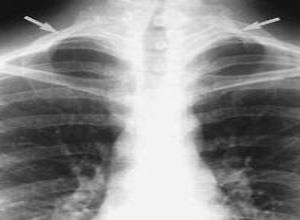

简介大部分人的颈肋退化了,但在部分人中(0.5%)还存留有颈肋,有颈肋的人并非都有症状。畸形的颈肋其长短的变化很大,按其形状可分为四类:1.小结节状,在第7颈椎横突的外方突出。2.不完整的颈肋,以纤维束与第一肋骨相连。3.完整的肋骨,以关节面与第一肋骨相连。4.完整的肋骨,以软骨与第一肋骨与胸骨相连。第七颈椎发生的颈肋很易出现症状,颈肋可发生于颈椎第六、第五,但极为少见。颈肋综合征很少发生于30岁以下的人。